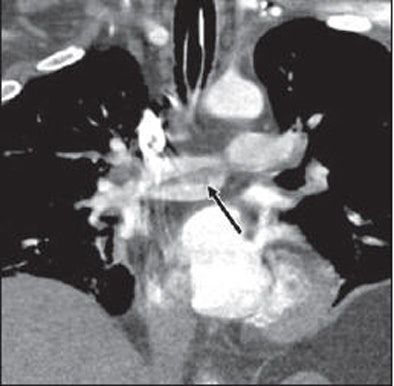

Pulmonary emboli were seen on CT in five of 14 (36%) ICU patients, the authors reported. These included a large saddle embolus straddling the bifurcation of the main pulmonary artery in one patient, which required an interventional procedure for mechanical fragmentation of the embolus.

| Twenty-eight-year-old man with laboratory-confirmed S-OIV (H1N1) requiring advanced mechanical ventilation with adverse outcome. Coronal reformatted image from contrast-enhanced chest CT examination shows saddle embolus (arrow) straddling bifurcation of main pulmonary artery. |

Also found at CT were a lobar emboli in one patient, segmental emboli in two patients, and subsegmental emboli in one patient. Two patients had deep venous thombosis in the leg veins at indirect CT venography that was confirmed on ultrasound.